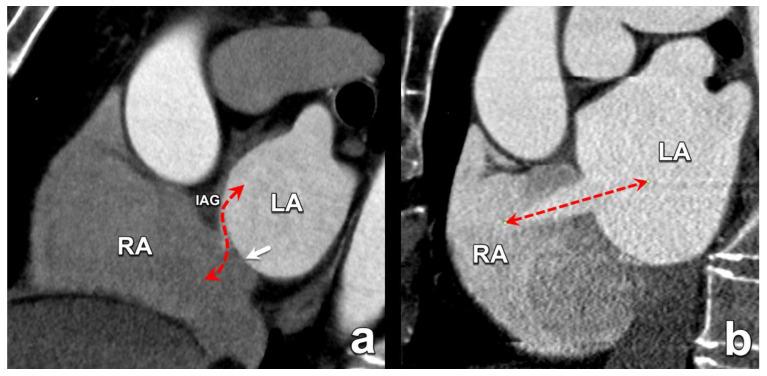

在过去十年中,多项试验和观察性研究证实,微创心脏介入治疗作为各种心脏病的可行治疗选择是有效的。在某些患者群体中,用于严重主动脉瓣狭窄的经导管技术已迅速成为外科主动脉瓣置换术的替代方法。此外,针对影响其他心脏瓣膜(如二尖瓣)的病症,非手术治疗选择也有所增加。这些新兴的微创介入治疗补充了已成熟的血管内技术,用于治疗心房颤动患者的房间隔缺损封堵、左心耳封堵和肺静脉隔离等疾病。鉴于这些手术的非手术性质以及缺乏对目标解剖结构的直接可视化,这些手术严重依赖精确的术前放射影像学检查,以实现最佳的患者选择和手术成功。本文基于作者的专家意见和详尽的文献研究。本手稿回顾了最常用的微创心脏介入治疗,强调了术前成像的基本信息以及放射学报告中必须包含的关键方面,以减少潜在并发症。准确的术前成像对于确保微创心脏介入治疗的安全有效至关重要,这突出了放射科医生在这些患者术前检查中的重要性。